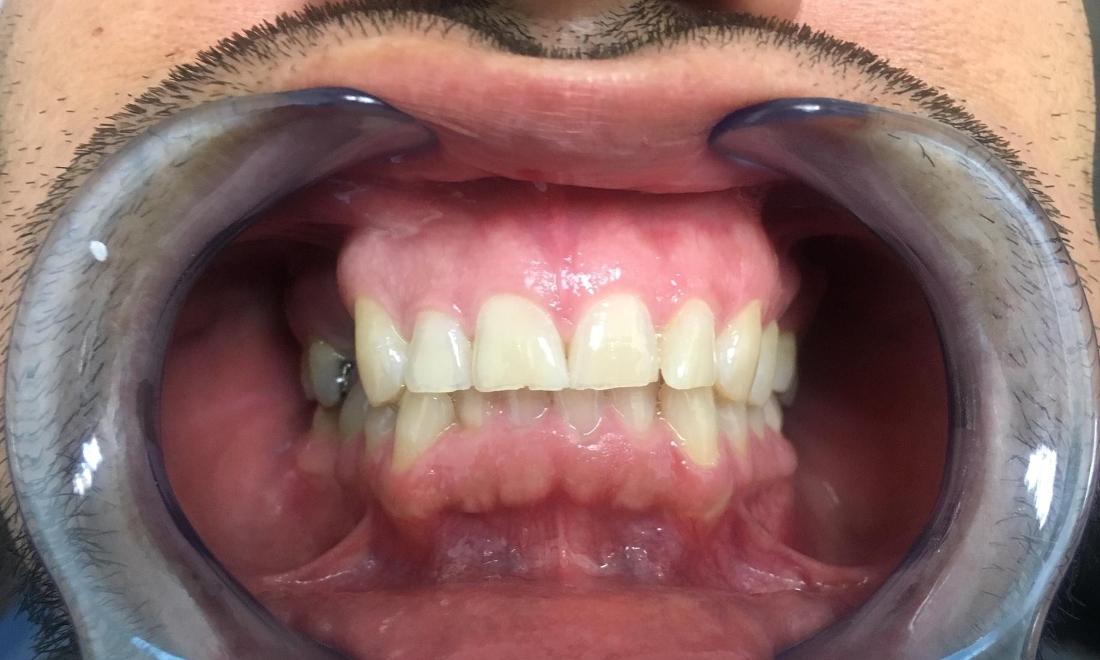

This patient was suffering from multiple areas of missing teeth. The patient was not a candidate for dental implants due to severe bone loss in the area. We utilized fixed bridges to replace multiple missing teeth in just 2 visits.